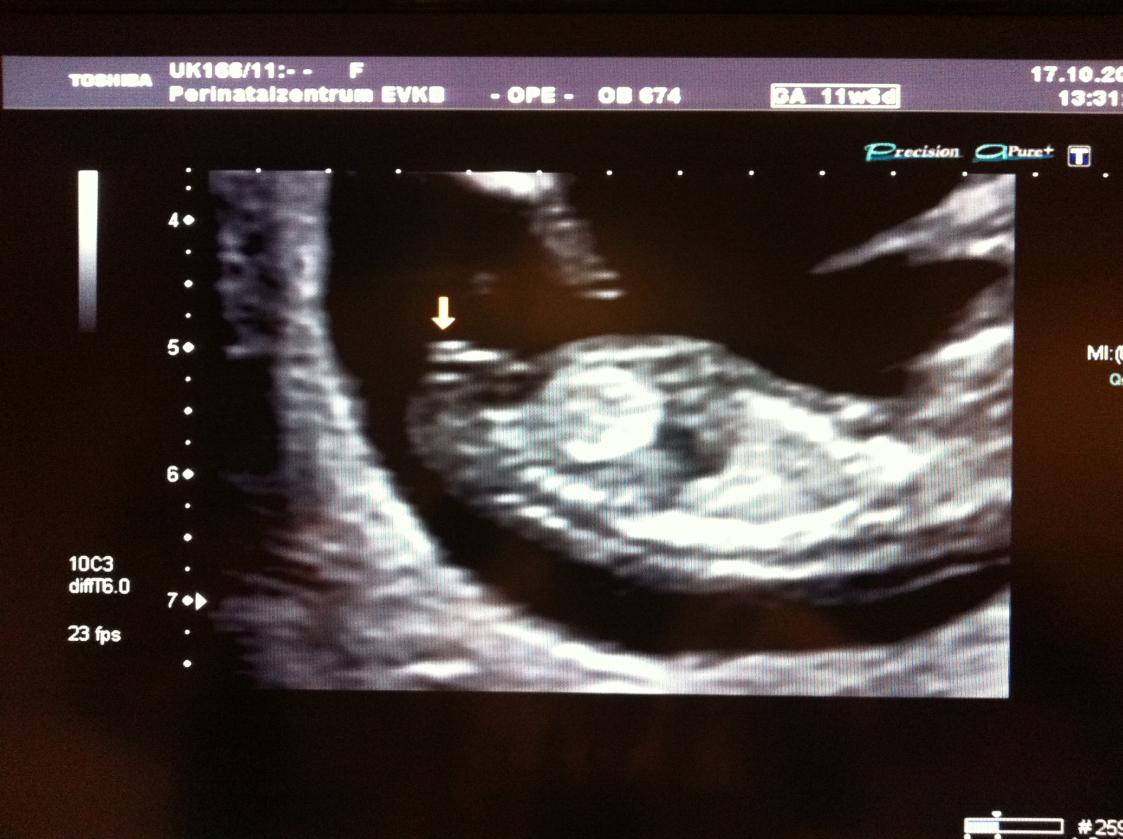

Hi ladies, i was wondering if someone has any ideas? The sonographer guessed 90% of a certain gender but what do you think? Thank you for looking xx

Attachment 666Attachment 667

I really hope your right girls. I have two boys and it's our last baby. He thought 90% girl which I thought was quite high this early? X

Yes it was my NT scan too. Hope it's right xx

Boy? I was hoping girl lol, consultant reckons 90% girl, hope he is right